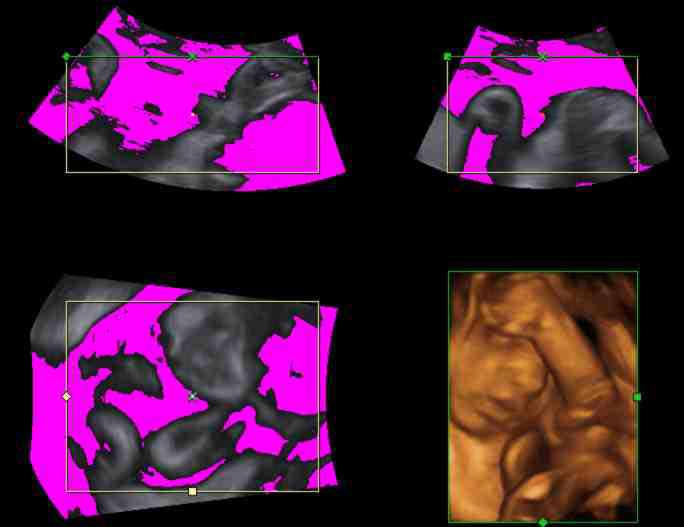

Refer to caption

Figure 6: The parameter Ithreshsubscript𝐼𝑡𝑟𝑒𝑠I_{thresh} determines which echo intensity values to render transparent. A user control with immediate feedback, indicating transparent regions in pink, is essential.

The most commonly used OTF in volume rendering of B–mode data assigns voxels to one of three classes depending on their echogenicity, namely invisible, transparent, and opaque. The corresponding piecewise linear OTF is modified manually by means of two parameters, namely a threshold intensity Itreshsubscript𝐼𝑡𝑟𝑒𝑠I_{tresh} and a transparency value α𝛼\alpha controlling the increase of opacity for intensities above Ithreshsubscript𝐼𝑡𝑟𝑒𝑠I_{thresh}. The effect of modifying Ithreshsubscript𝐼𝑡𝑟𝑒𝑠I_{thresh} is depicted visually on MPR images, see Fig.6.

The parameters of the OTF affect the rendered image in a substantial way: The lower Ithreshsubscript𝐼𝑡𝑟𝑒𝑠I_{thresh}, the lower the rendered image’s brightness, due to an increasing number of hypoechoic voxels contributing to the image. Furthermore, the OTF affects depth contrast, i.e., the contrast arising from a spatial discontinuity in the target structure, and tissue contrast, i.e., contrast due to different echogenicity of adjacent tissue. See honigmann03 for an evaluation of these effects on linear and parabolic OTFs. On the other hand, any modification of fundamental acquisition parameters, such as, e.g., overall gain, or depth gain compensation, and any change of the position of the transducer or the target structure, changes the echogenicity distribution and thus requires modifying the OTF for an optimum visualization. Obviously, for a real time imaging modality incessant modification is not feasible. Hence, in clinical practice sonographers use a default OTF providing reasonable visualization in the majority of cases, and hardly ever touch the OTF control panel.